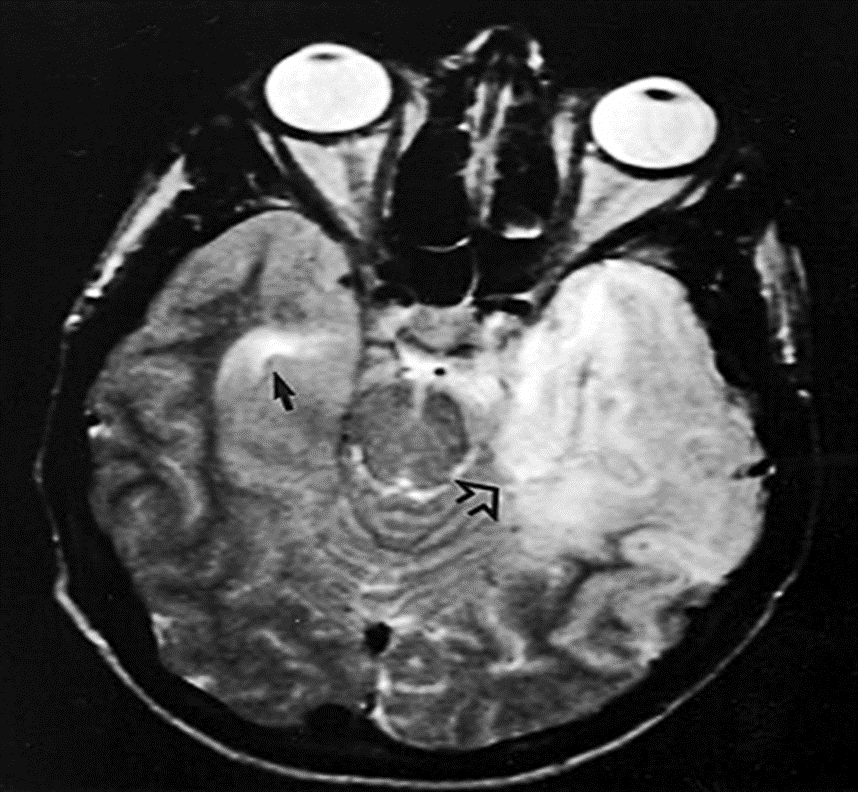

• ვირუსული ეტიოლოგიის მიხედვით მიღებული მონაცემები – მაგნიტურ-რეზონანსული ტომოგრაფიის მონაცემები გარკვეულწილად განსხვავდება ვირუსული ეტიოლოგიების მიხედვით. თუმცა, HSV ენცეფალიტის დროს საფეთქლის წილის ლოკალიზაციის გარდა, უმეტესი მონაცემები არ არის მაღალმგრძნობიარე ან სპეციფიკური კონკრეტული პათოგენისთვის.

–HSV – საფეთქლის წილის ლოკალიზაცია (სურათი 1); საფეთქლის ლოკალიზაცია ასევე შეიძლება მოხდეს სხვა ჰერპესვირუსებთან და სიფილისთან [35]. (იხილეთ „ჰერპეს სიმპლექსის ვირუსის ტიპი 1 ენცეფალიტი“, განყოფილება „ვიზუალიზაციის კვლევები“ და „ახალშობილთა ჰერპეს სიმპლექსის ვირუსის (HSV) ინფექცია: კლინიკური მახასიათებლები და დიაგნოზი“, განყოფილება „ნეიროვიზუალიზაცია“.)

(სურათი 1)ჰერპესვირუსული ენცეფალიტი მაგნიტურ-რეზონანსულ ტომოგრაფიაზე

T2-შეწონილი მაგნიტურ–რეზონანსული ტომოგრაფია აჩვენებს მთელ მარცხენა საფეთქლის წილის შეშუპებას, ასევე ქერქისა და თეთრი ნივთიერების პათოლოგიურ ჰიპერინტენსივობას შეშუპების გამო (ღია ისარი). გარდა ამისა, მსგავსი, მაგრამ ნაკლებად ინტენსიური ცვლილებებია მარჯვნივ (პატარა ისარი).